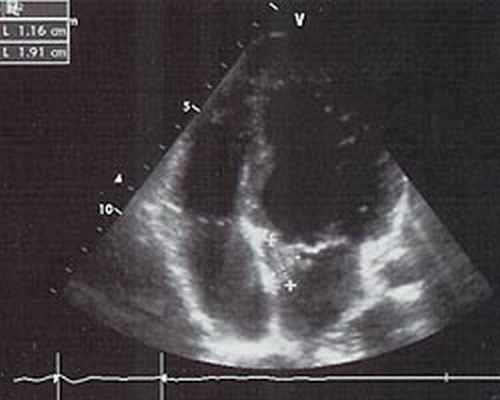

Трансторокальная ЭхоКГ ( 11.03.08): у основания передней створки митрального клапана со стороны левого предсердия конгломерат вегетаций размером 1,9х1,1 см, митральная регургитация 3 ст.